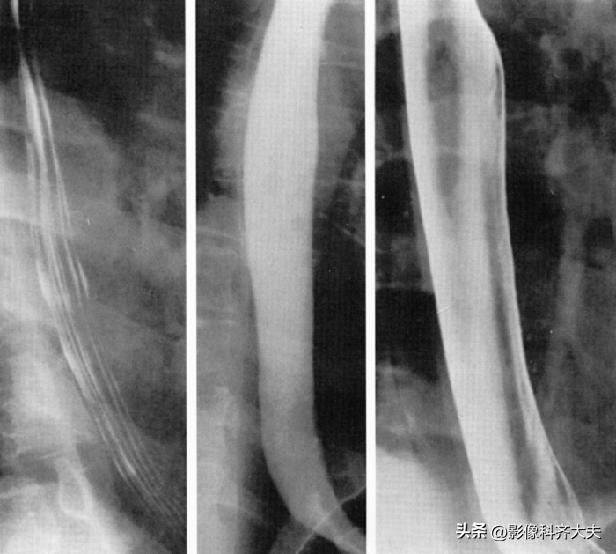

胃双对比相(仰卧右前斜位)

胃双对比相(仰卧左前斜位)